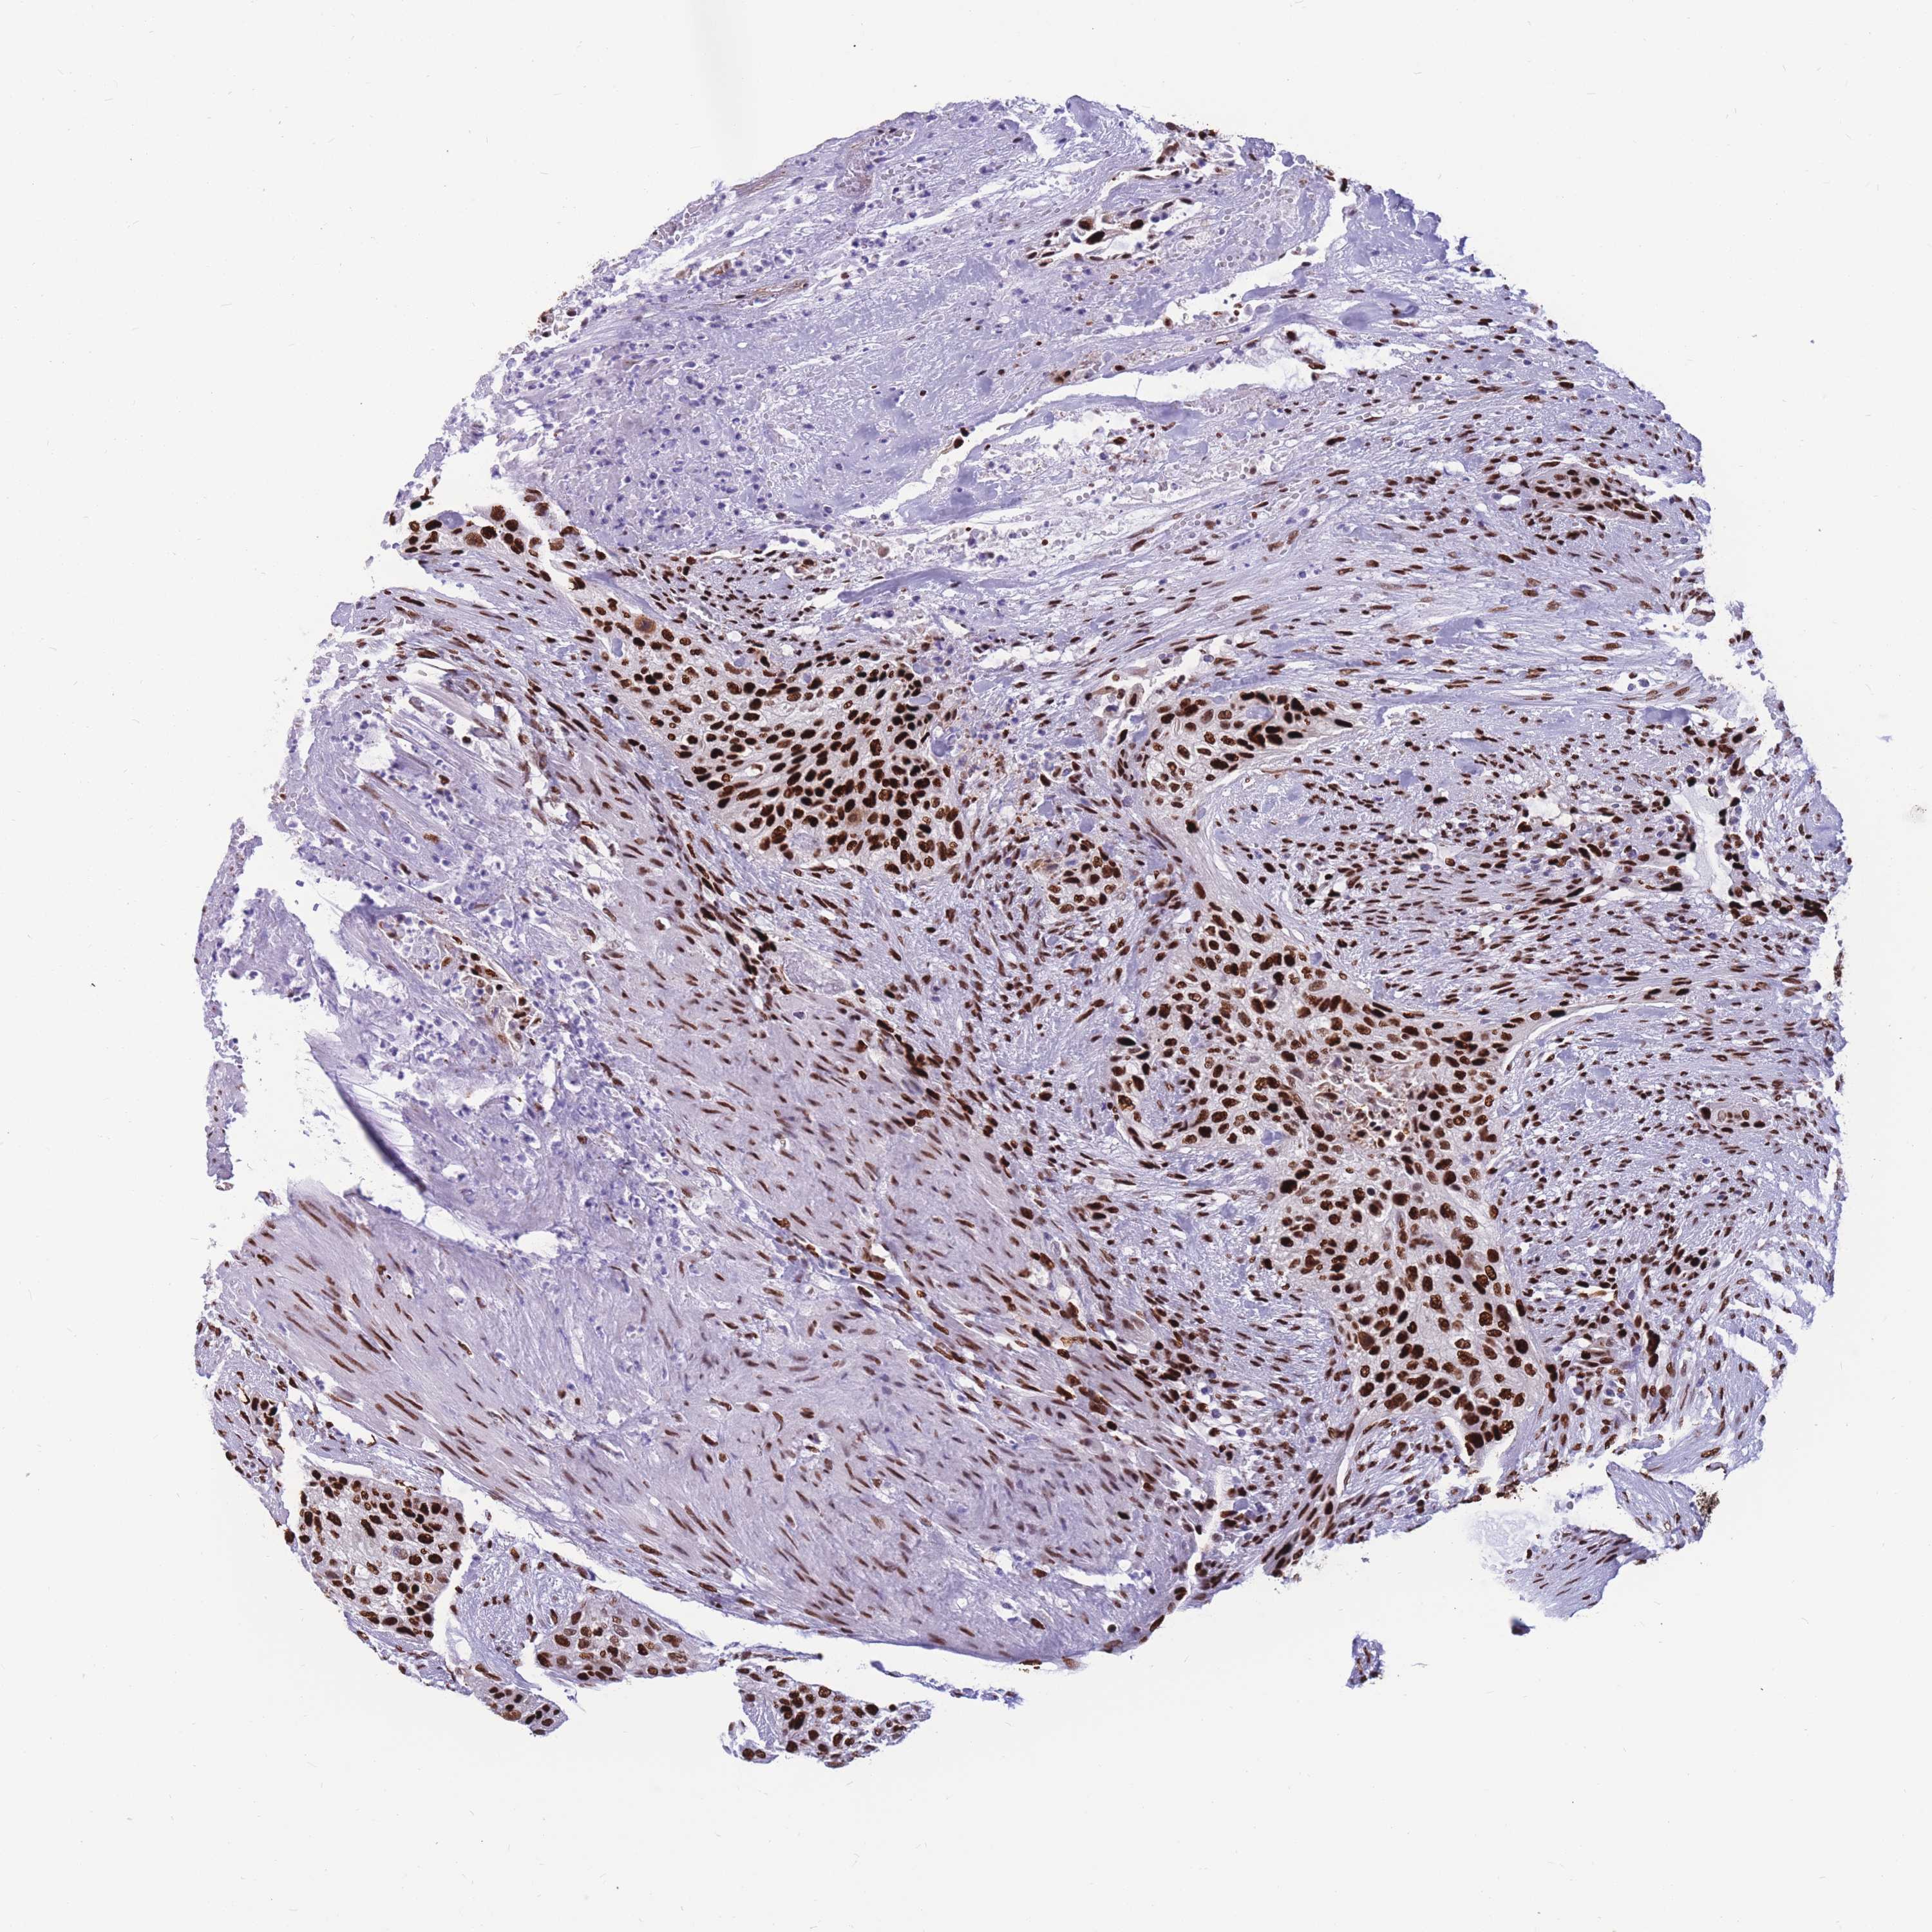

UROTHELIAL CANCER - Protein expressioni

A mouse-over function shows sample information and annotation data. Click on an image to view it in a full screen mode. Samples can be filtered based on level of antibody staining by selecting one or several of the following categories: high, medium, low and not detected. The assay and annotation is described here.

Note that samples used for immunohistochemistry by the Human Protein Atlas do not correspond to samples in the TCGA dataset.

Antibody stainingi

Antibody staining in the annotated cell types in the current human tissue is reported as not detected, low, medium, or high, based on conventional immunohistochemistry profiling in selected tissues. This score is based on the combination of the staining intensity and fraction of stained cells.

Each image is clickable and will lead to virtual microscopy that enables deeper exploration of all samples and also displays staining intensity scores, fraction scores and subcellular localization as well as patient and tissue information for each sample.

Antibody HPA028136

Antibody HPA030518

Antibody HPA030520

Staining

High

Medium

Low

Not detected

Intensity

Strong

Moderate

Weak

Negative

Quantity

>75%

75%-25%

<25%

None

Location

Nuclear

Cytoplasmic/membranous

Cytoplasmic/membranous,nuclear

Urothelial carcinoma, Low grade

Urothelial carcinoma, High grade